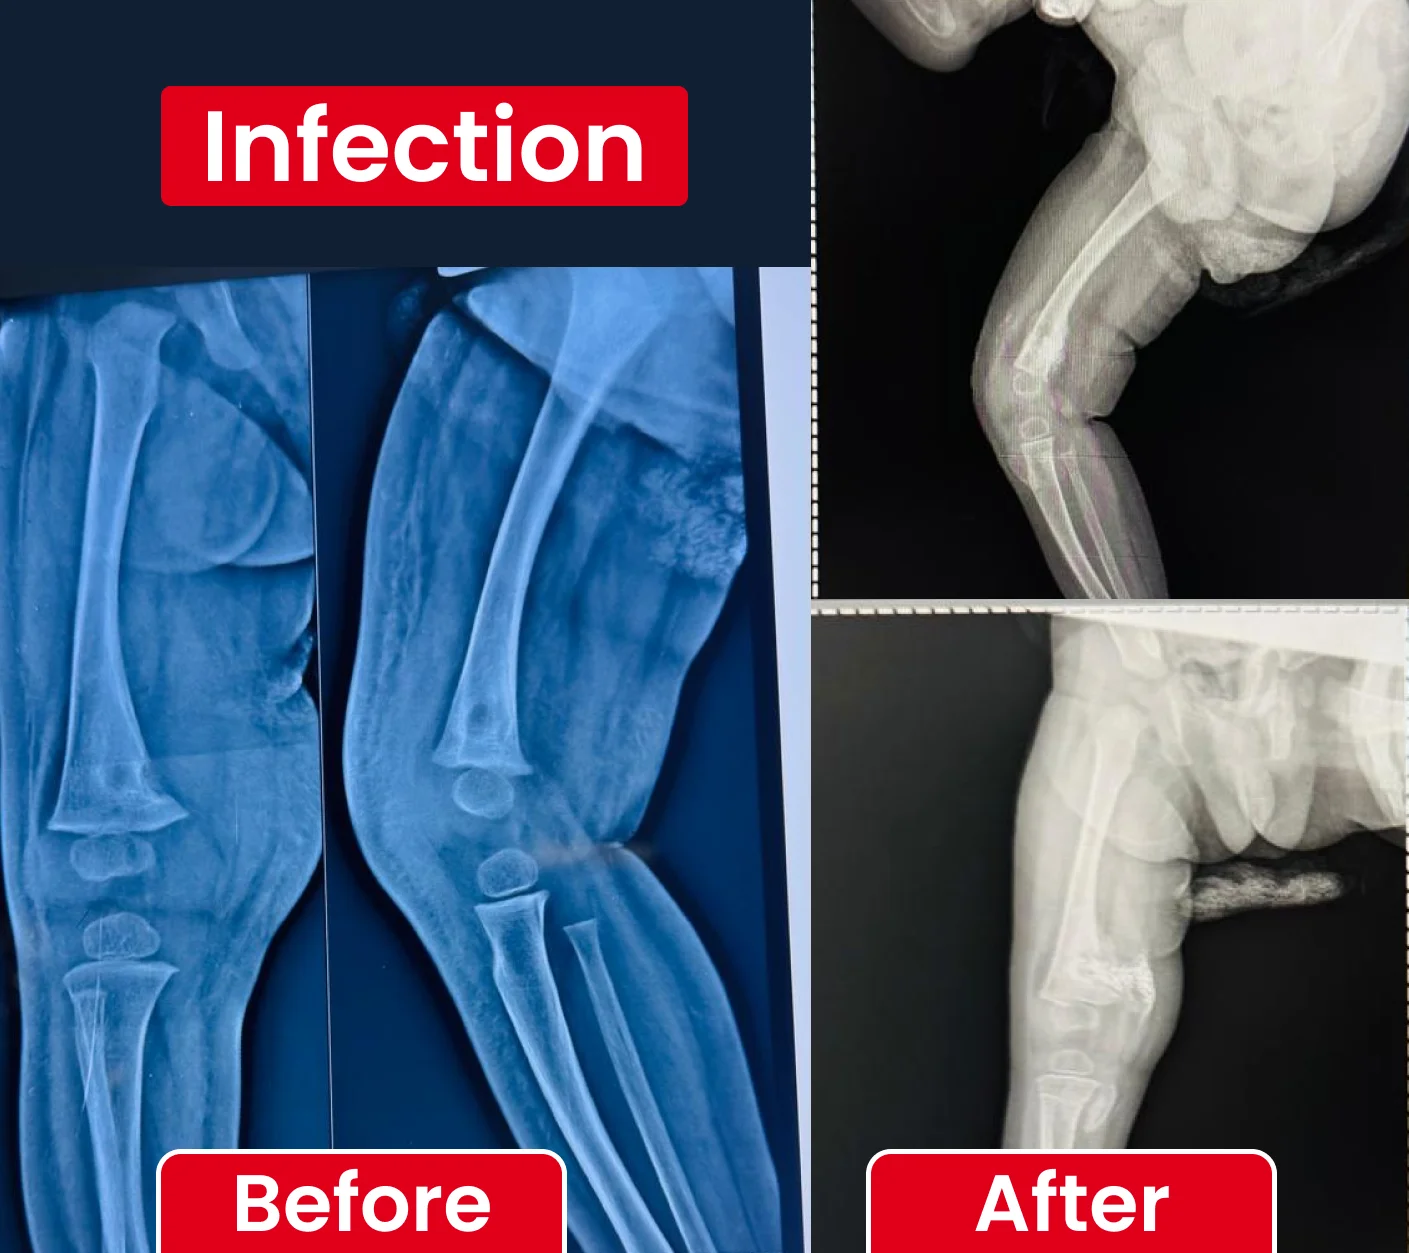

Timely diagnosis and treatment of paediatric bone infections to prevent long-term damage and support recovery.

Paediatric Orthopaedic Cases Treated